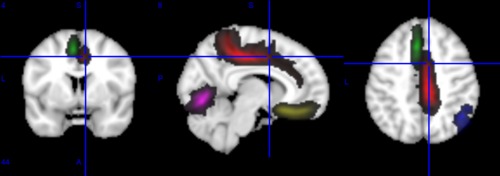

Outlines

The outline at 50% of all the structures